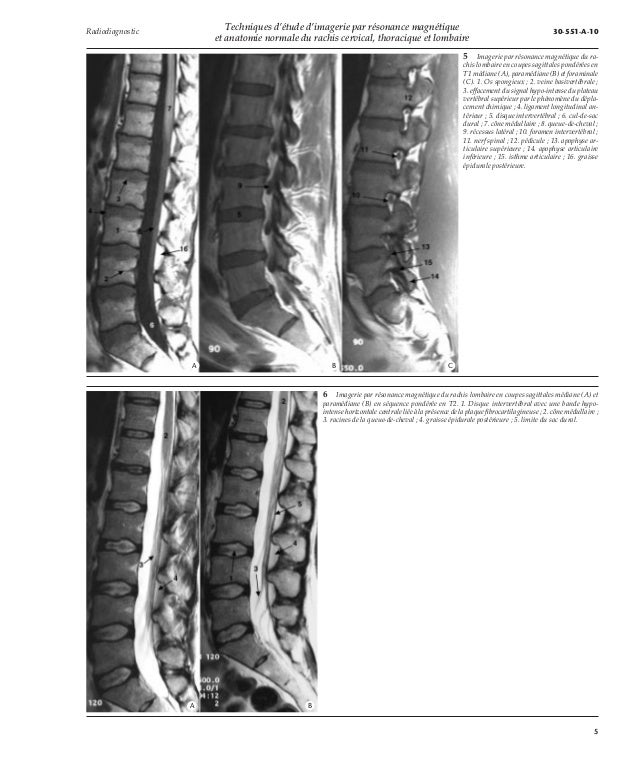

Techniques D Etude D Irm Et Anatomie Normale Du Rachis Cervi